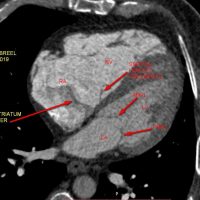

0Neonate with such HLHS Hypoplastic LV, LVOT & AORTA Ductus dependent systemic circulation. [gallery ids="18820,18823"] Mohamed Gibreel , FEBR (Fellowship of Egyptian Board of Radiology ) Cardiac imaging consultant at..